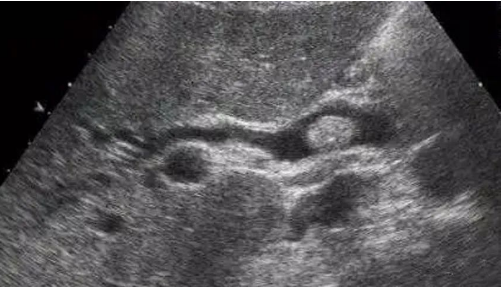

此时,通过超声辅助检查,可提早发现胆囊是否增大、胆囊壁是否增厚。

大的结石堵在胆囊出口,小一点的堵在胆总管,那么更小的呢?这样的结石称为“泥沙样结石”,超声下可发现,它们可以顺利达到胆总管的开口,而胆总管的开口在十二指肠,旁边紧挨着的就是胰腺管道胰管的开口,于是,接下来这些很小的结石可以更加顺利地进入胰管,诱发“胆源性胰腺炎”。